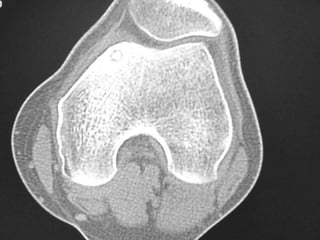

Osteoid Osteoma - CT

• CT is more accurate than MRI.

• CT helped in confirming the diagnosis of

osteoid osteoma in 74% of cases.

• Szendroi et al reported accuracies of about

66% in the diagnosis of intra-articular lesions

and 90% in extra-articular lesions.

• To date, CT scanning is the primary

investigational tool for the definitive diagnosis

of osteoid osteoma.

Osteoid Osteoma -CT • CT is more accurate than MRI. • CT helped in confirming the diagnosis of osteoid osteoma in 74% of cases. • Szendroi et al reported accuracies of about 66% in the diagnosis of intra-articular lesions and 90% in extra-articular lesions. • To date, CT scanning is the primary investigational tool for the definitive diagnosis of osteoid osteoma.